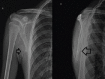

Case report: We have included five cases of osteochondromas occurring at rare locations with variable presentations and their management. We have included one case of metacarpal, one case of skull exostosis, two cases of scapula exostosis, and one case of fibula exostosis.